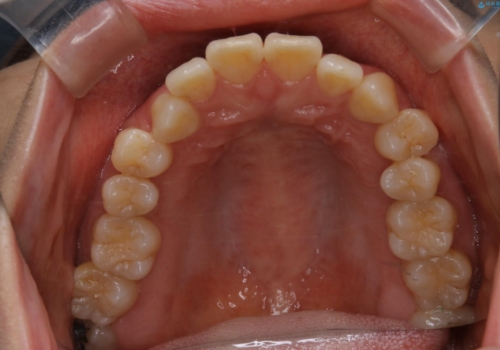

- 前歯のがたつきが気になるとご相談にいらした方です。右側前歯部のクロスバイトの他、左側にもシザーズバイトが認められたため、インビザラインにて治療を行いました。出産直後のため、ご自身の時間がなかなか取れないとの事で、最小限の来院回数で治療を勧められるように計画しました。

患者様ご自身で使用時間をしっかり管理して頂くことを条件に、最低限の来院回数で治療を進めていきました。20時間以上の使用を厳守して頂けたことで、少ない来院回数にて治療を終了することが出来ました。前よりも噛みやすくなったと大変喜んでいただけました。